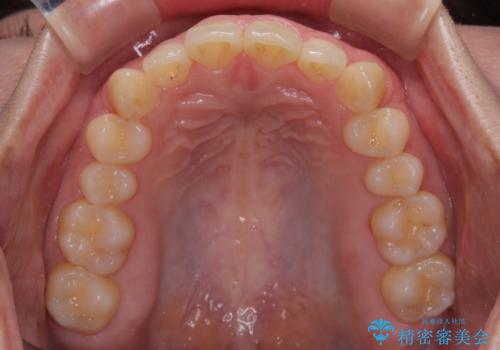

- 下顎前歯が完全に隠れてしまっていることを気にして来院された患者様です。

下顎の臼歯が手前に傾斜していることで咬み合わせが深くなってしまい、下顎前歯が見えないほどに上顎前歯が覆い被さっている状態でした。

咬合力が強いことと、マウスピースを長時間装着する自信がないとのことで、ワイヤー装置にて矯正治療を行うこととしました。

下顎臼歯を起き上がらせるためにユーティリティーアーチを使用し、一気に深い咬み合わせを改善することができました。